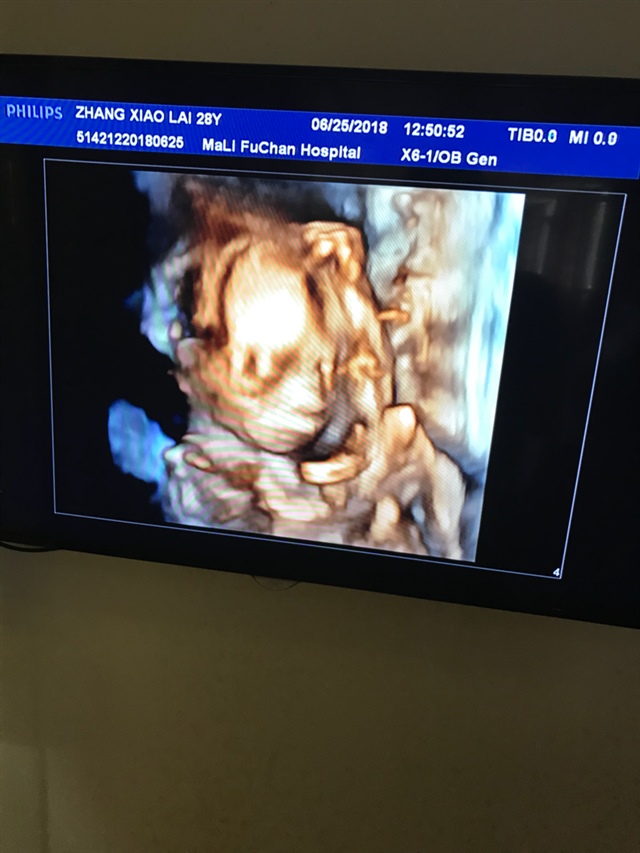

这是几维,画质看着有点恐怖

小小的世界[帖主]:今天做四维,医生不说,男女都一样,不过挺好奇